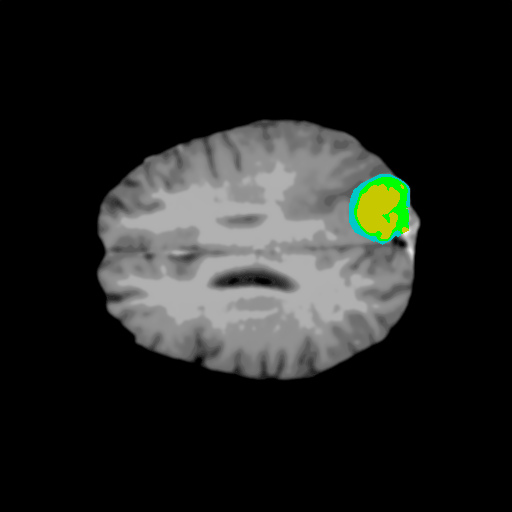

Extensive experiments have been performed in the current setup, and experimental outcomes are reported with the demonstration of numerical and statistical analyses using the proposed QFS-Net, QIS-Net [39], convolutional U-Net [18] and Residual U-Net (URes-Net) architectures [20]. The human expert segmented skull-tripped contrast enhanced DSC brain MR input image slices of size and ROIs are provided in Figure 5 as samples. The demonstration of QFS-Net segmented images followed by the essential post-processed outcome on the slice no. for class level with four distinct activation schemes () are shown in Figure 6. It is evident from the experimental data provided in Table LABEL:tab1 that the proposed QFS-Net performs optimally for the -connected quantum fuzzy pixel information heterogeneity assisted activation () with and gray scale set in comparison with other thresholding schemes and gray scale sets under the four evaluation parameters () [44]. The segmented tumors obtained using the proposed self-supervised procedure under class transition levels with four different thresholding schemes , , and are demonstrated in Figures 7- 8 for the class boundary sets and [39], respectively. The segmented images using the remaining two class boundary sets ( and ) [39] are provided in the supplementary materials section. The segmented ROIs describing the whole tumor region after the masking procedure using QIS-Net, U-Net and URes-Net are also reported in Figure 9.